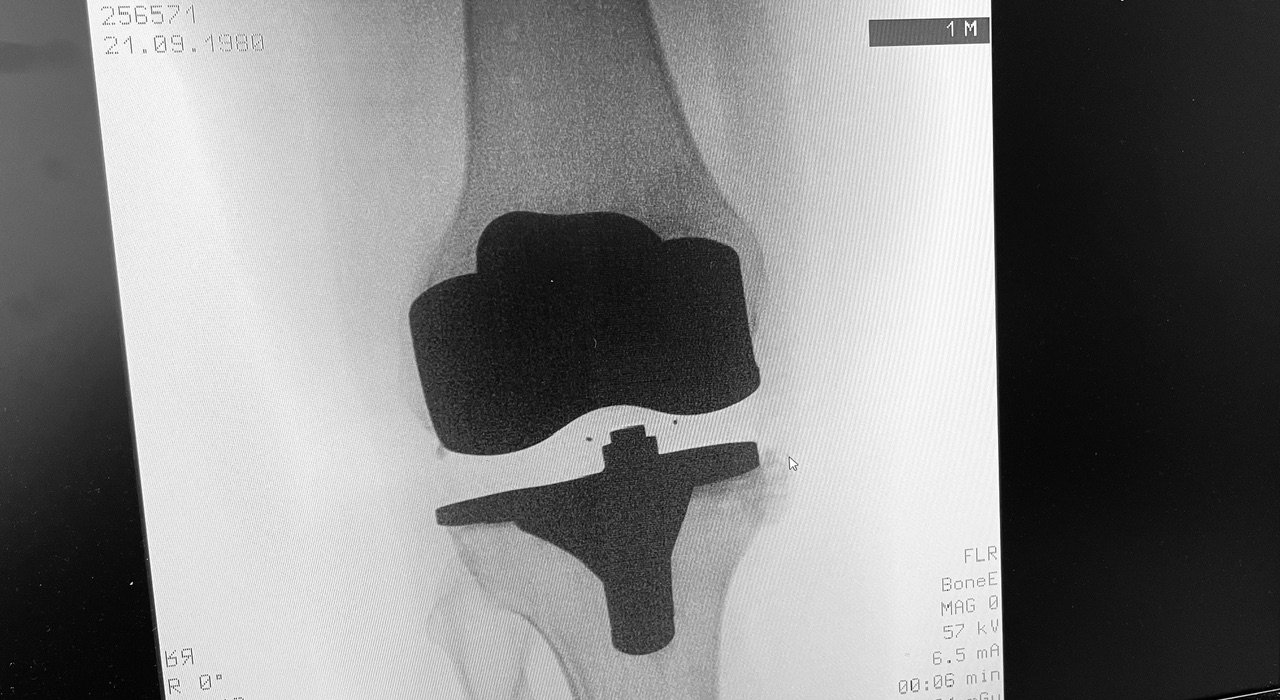

Η ολική αρθροπλαστική γόνατος είναι χειρουργική επέμβαση κατά την οποία αντικαθίσταται η φθαρμένη άρθρωση του γόνατος με τεχνητά εμφυτεύματα.

Στόχος είναι η ανακούφιση από τον πόνο, η βελτίωση της κίνησης και η αποκατάσταση της λειτουργικότητας του γόνατος.

Κατά την ολική αρθροπλαστική:

• αφαιρούνται οι φθαρμένες αρθρικές επιφάνειες

• τοποθετούνται μεταλλικά εμφυτεύματα στο μηριαίο οστό και την κνήμη

• παρεμβάλλεται ειδικό ένθετο πολυαιθυλενίου

• σε επιλεγμένες περιπτώσεις αντικαθίσταται και η επιγονατίδα